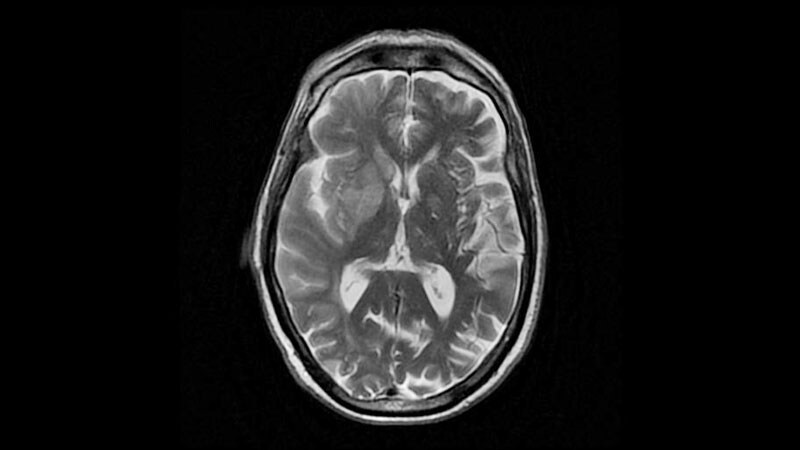

Earlier Anticoagulation Better After Ischemic Stroke in AF?The observational ATTUNE study suggests that starting anticoagulation within 4 days of stroke leads to fewer new infarcts

detected by imaging without an increase in hemorrhage compared with starting later.